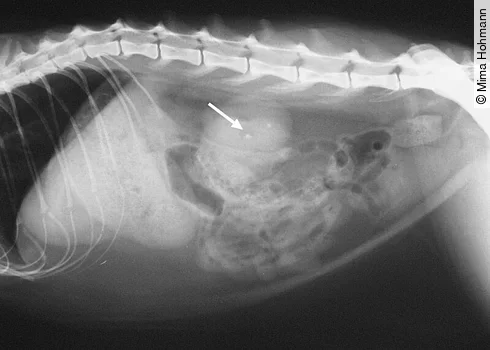

Schmerzen in der Wirbelsäule, meist im Übergang Lendenwirbelsäule/Kreuzbein ([Abb. 2])

Was kann man tun? Man sollte eine ausführliche klinische Untersuchung durchführen mit Harnuntersuchung und eventuell auch einem Röntgenbild, wenn man bei der Untersuchung Schmerzen und/oder muskuläre Verspannungen an den Gelenken ([Abb. 3]), der Wirbelsäule oder im Abdomen feststellt. Dabei sollten die Gelenke auch passiv durchbewegt werden.

Osteophytäre Erkrankungen der Gelenke und der Wirbelsäule werden bei der Katze oft unterschätzt. Prävalenz der Osteoarthrose bei der Katze, dabei sind am häufigsten betroffen:

Im Alter leiden über 50 % der Katzen unter Osteoarthrose (DVG-Tagung Berlin, November 2016). Hier einige Beispiele für die Osteoarthrose bei der Katze:

Wie man sieht, sollte man eine Katze, die sich die Haare am Abdomen ableckt, auf alle Fälle röntgen. Der Vorteil des Röntgens: Man sieht nicht nur die Veränderungen an den Gelenken und der Wirbelsäule, sondern auch die Obstipation, Kristalle, Blasen-, Nieren- und Gallensteine, sondern auch Neoplasien, die ebenfalls ausstrahlende Schmerzen verursachen können.